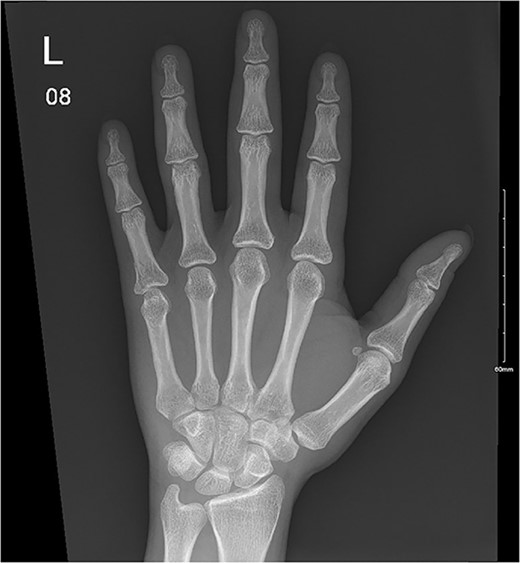

A 32-year-old male presented to the emergency department with a painful, discolored, and edematous left thumb following spontaneous deployment of his automobile’s airbag. On physical examination, the thumb’s range of motion (ROM) was reduced because of pain. Radiography showed a tuft fracture of the thumb’s distal phalanx (Fig. 1). The patient was managed conservatively with a Zimmer splint and followed-up 1 week later. Magnetic resonance imaging (MRI) was obtained to assess for the presence of ligamentous injury showed complete tearing and proximal retraction of the distal attachment of the ulnar collateral ligament in (Fig. 2), so the patient was given a thumb spica and was booked for surgery. In the operating room, the ulnar collateral ligament was identified and was indeed completely avulsed from its distal attachment site. The ligament was repaired using the Kessler tendon repair maneuver, ultimately ending with the thumb flexed 30° at the metacarpophalangeal (MCP) joint. This patient was followed-up for 103 days after his first presentation. On his final clinic visit, the thumb was stable, the wound was fully healed, and full ROM was regained.

A comminuted slightly displaced fracture of the tip of the left fifth distal phalanx.